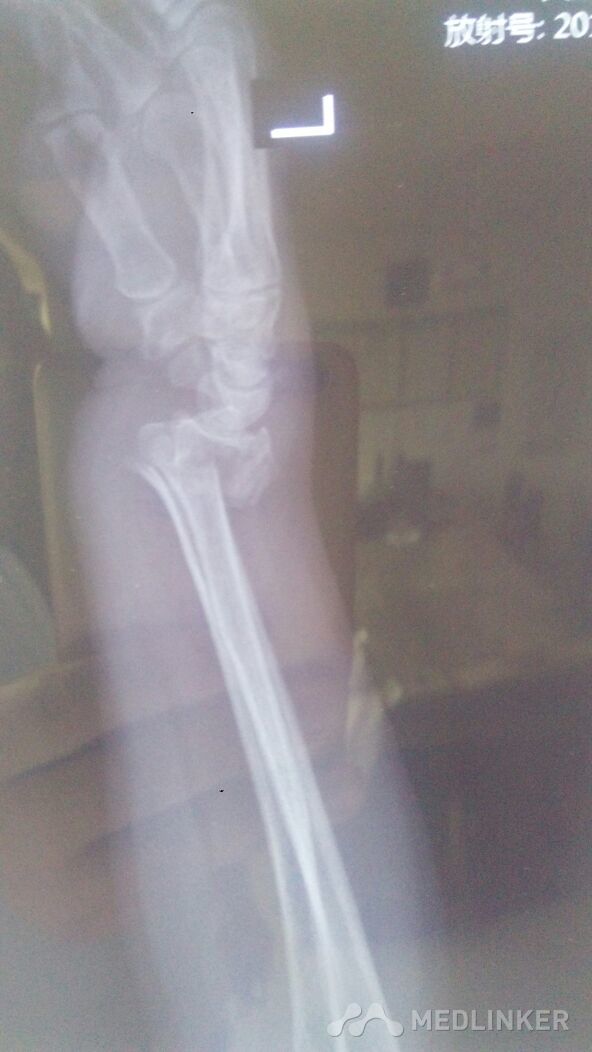

左桡骨远端骨折,左尺骨茎突骨折。

左腕部外伤后,血压高压210.低压110.左腕疼痛,畸形明显。手法复位。

左腕部外伤后,畸形明显伴疼痛。左手末梢感觉麻木。左腕部活动受限。

左桡骨远端骨折,左尺骨茎突骨折,手术治疗。

已经尽力了。尺偏,北侧仍然移位。血压太高。不手术治疗,不行啊!家属不愿手术治疗。怎么办?